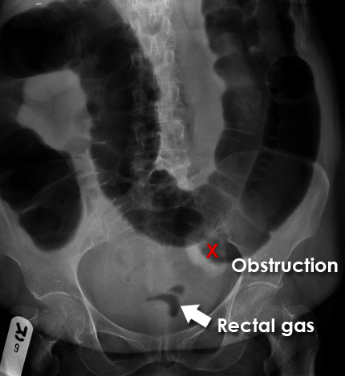

Describe what is depicted in this AXR [1]

Large bowel obstruction

• Here the colon is dilated down to the level of the distal descending colon. There is the impression of soft tissue density at the level of obstruction (X). No gas is seen within the sigmoid colon.

• Obstruction is not absolute in this patient as a small volume of gas has reached the rectum (arrow).

• An obstructing colon carcinoma was confirmed on CT and at surgery.